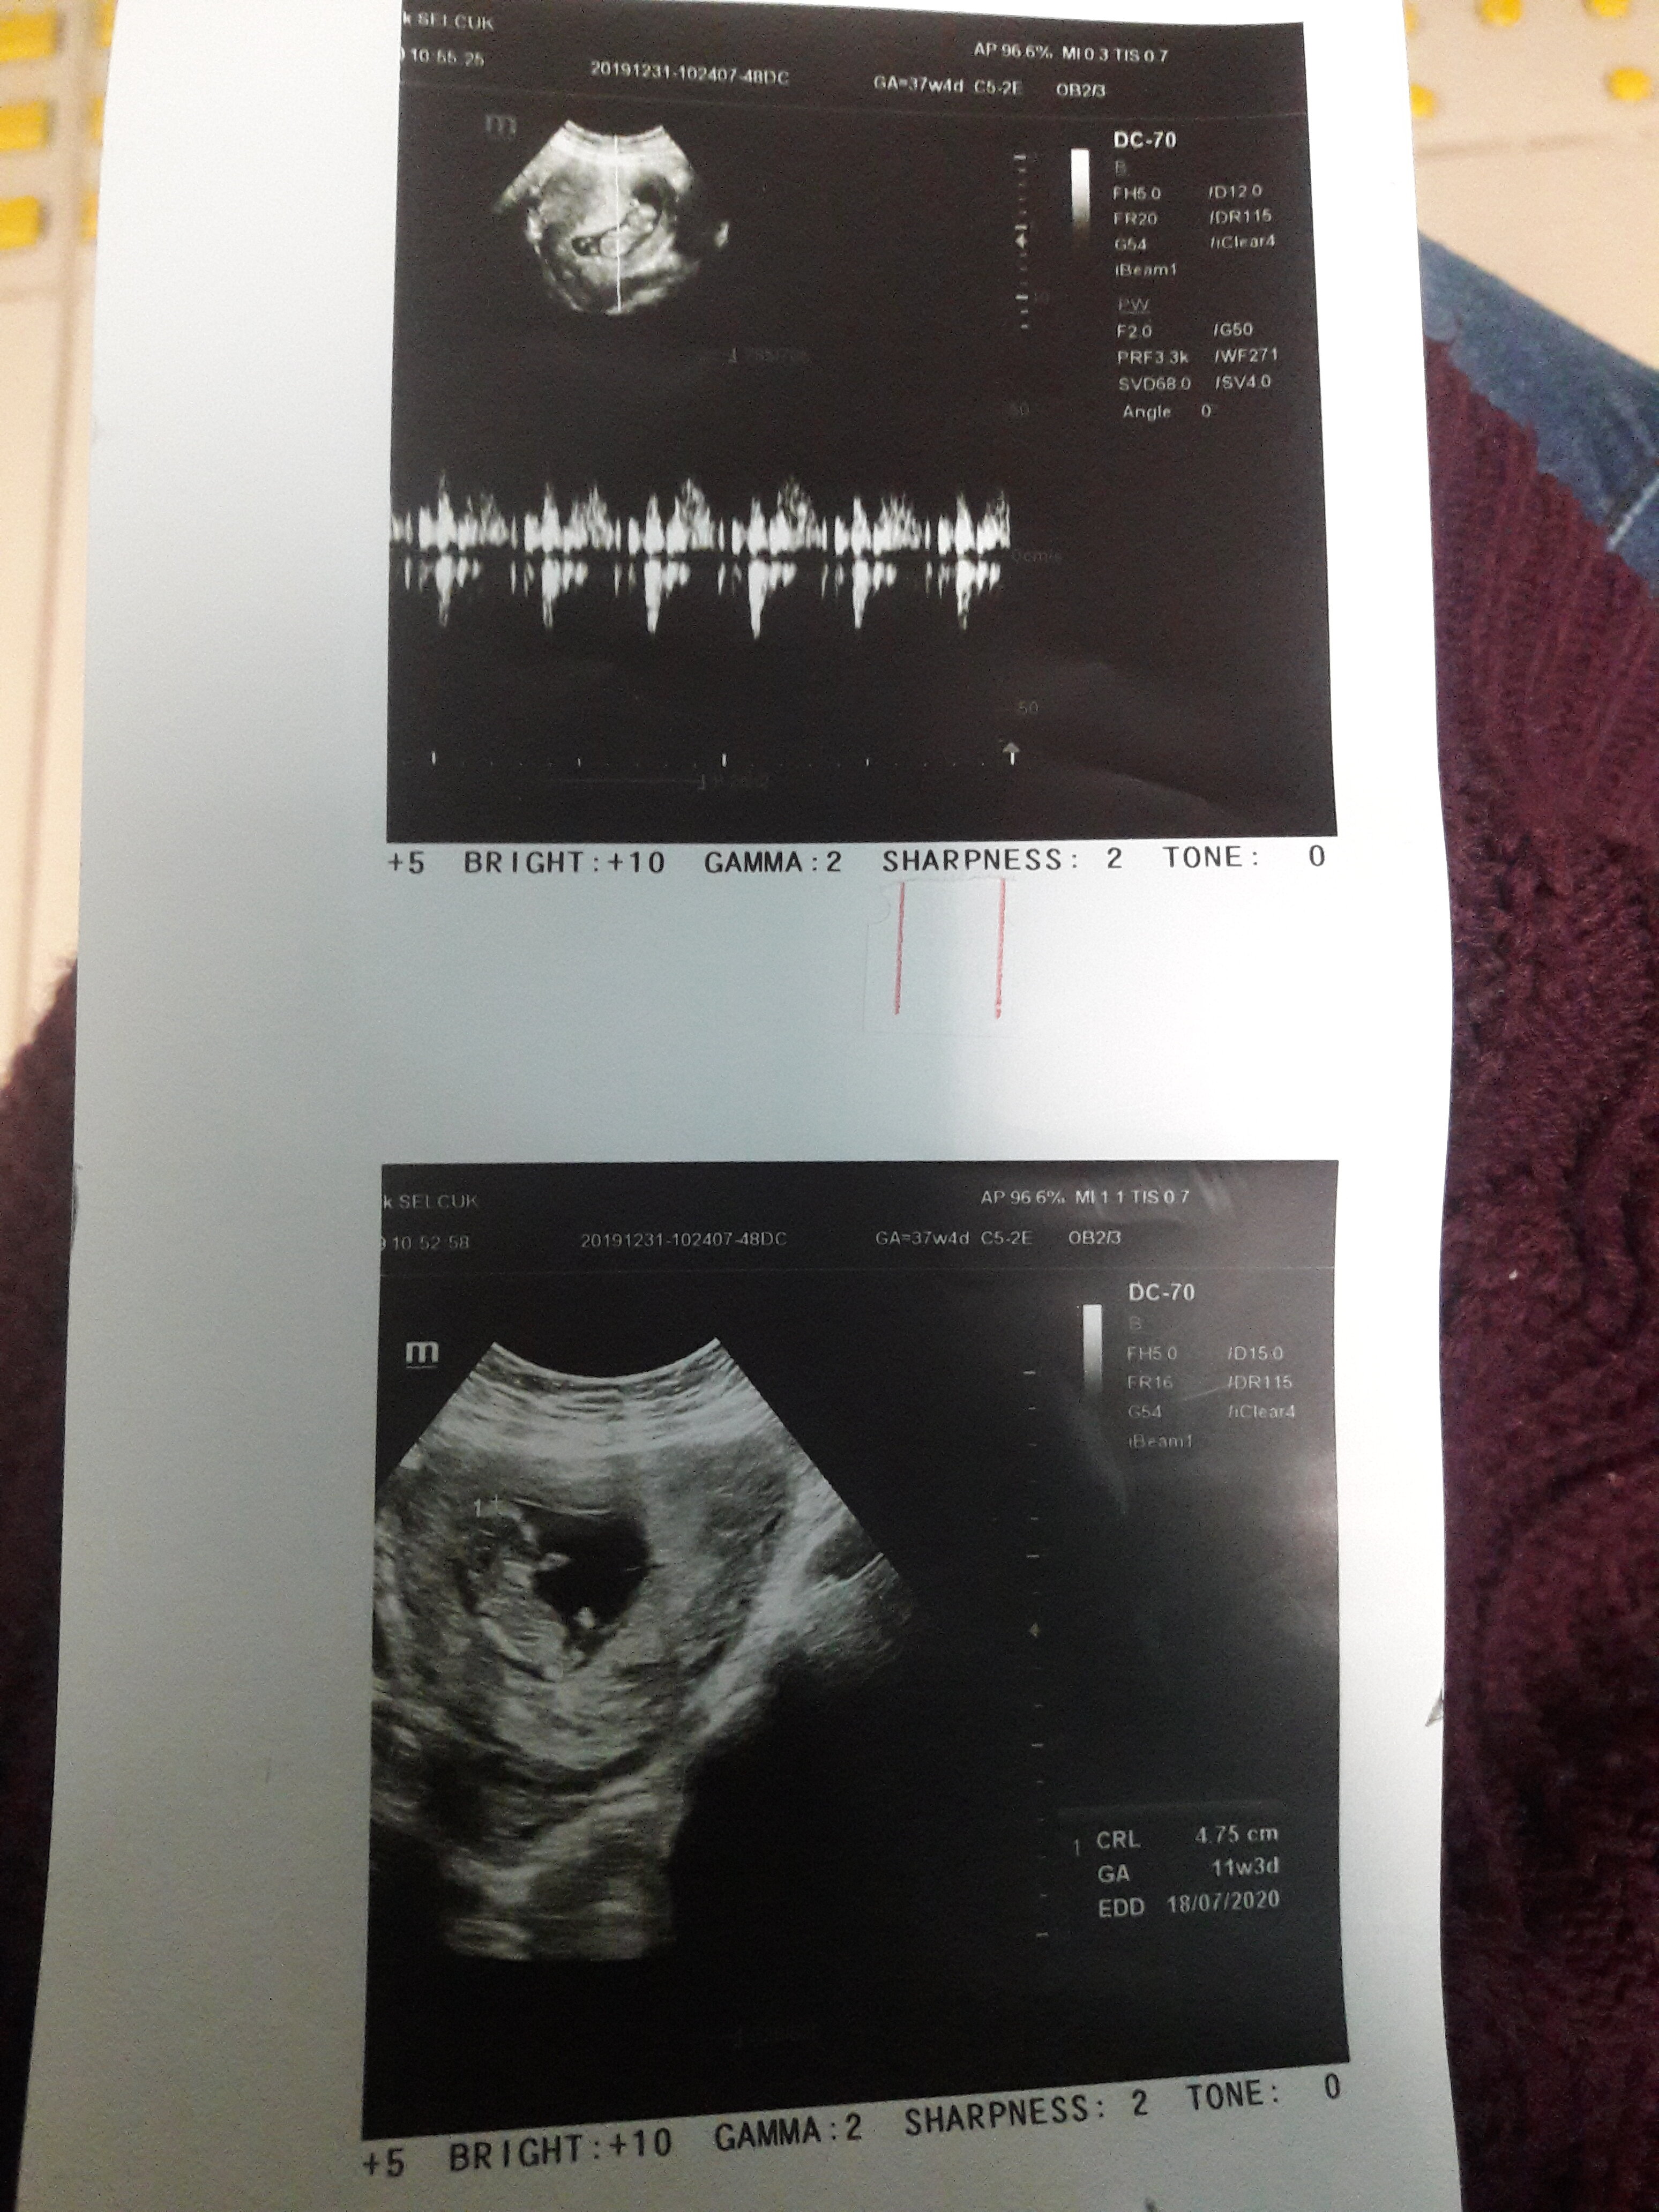

Sümbül 63 Yeni Üye Üye 1 Ocak 2020 #18 Merhabalar benimde usg goruntume yorum yapabilirmisiniz kizmi erkekmi sizce Ekli dosyalar 20191231_104945.jpg 1,5 MB · Görüntüleme: 480

SadmiN ♥ Evli Mutlu Çocuklu ♥ Yönetici 1 Ocak 2020 #19 Sevgili @Sümbül 63 malesef net değil dolayısı ile yorum yapamıyorum yakın lazım ve tabiki en önemlisi net lazım.

Sevgili @Sümbül 63 malesef net değil dolayısı ile yorum yapamıyorum yakın lazım ve tabiki en önemlisi net lazım.

Sümbül 63 Yeni Üye Üye 2 Ocak 2020 #20 Bu sekilde netmi acaba Ekli dosyalar 15779142171731587885330.jpg 1,3 MB · Görüntüleme: 433